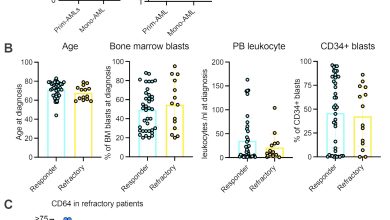

Identificado marcador para resposta terapêutica na leucemia mielóide aguda

Sensibilidade da linha celular e dados adicionais do paciente. Um IC50s para VEN de 19 linhagens de células AML classificadas…